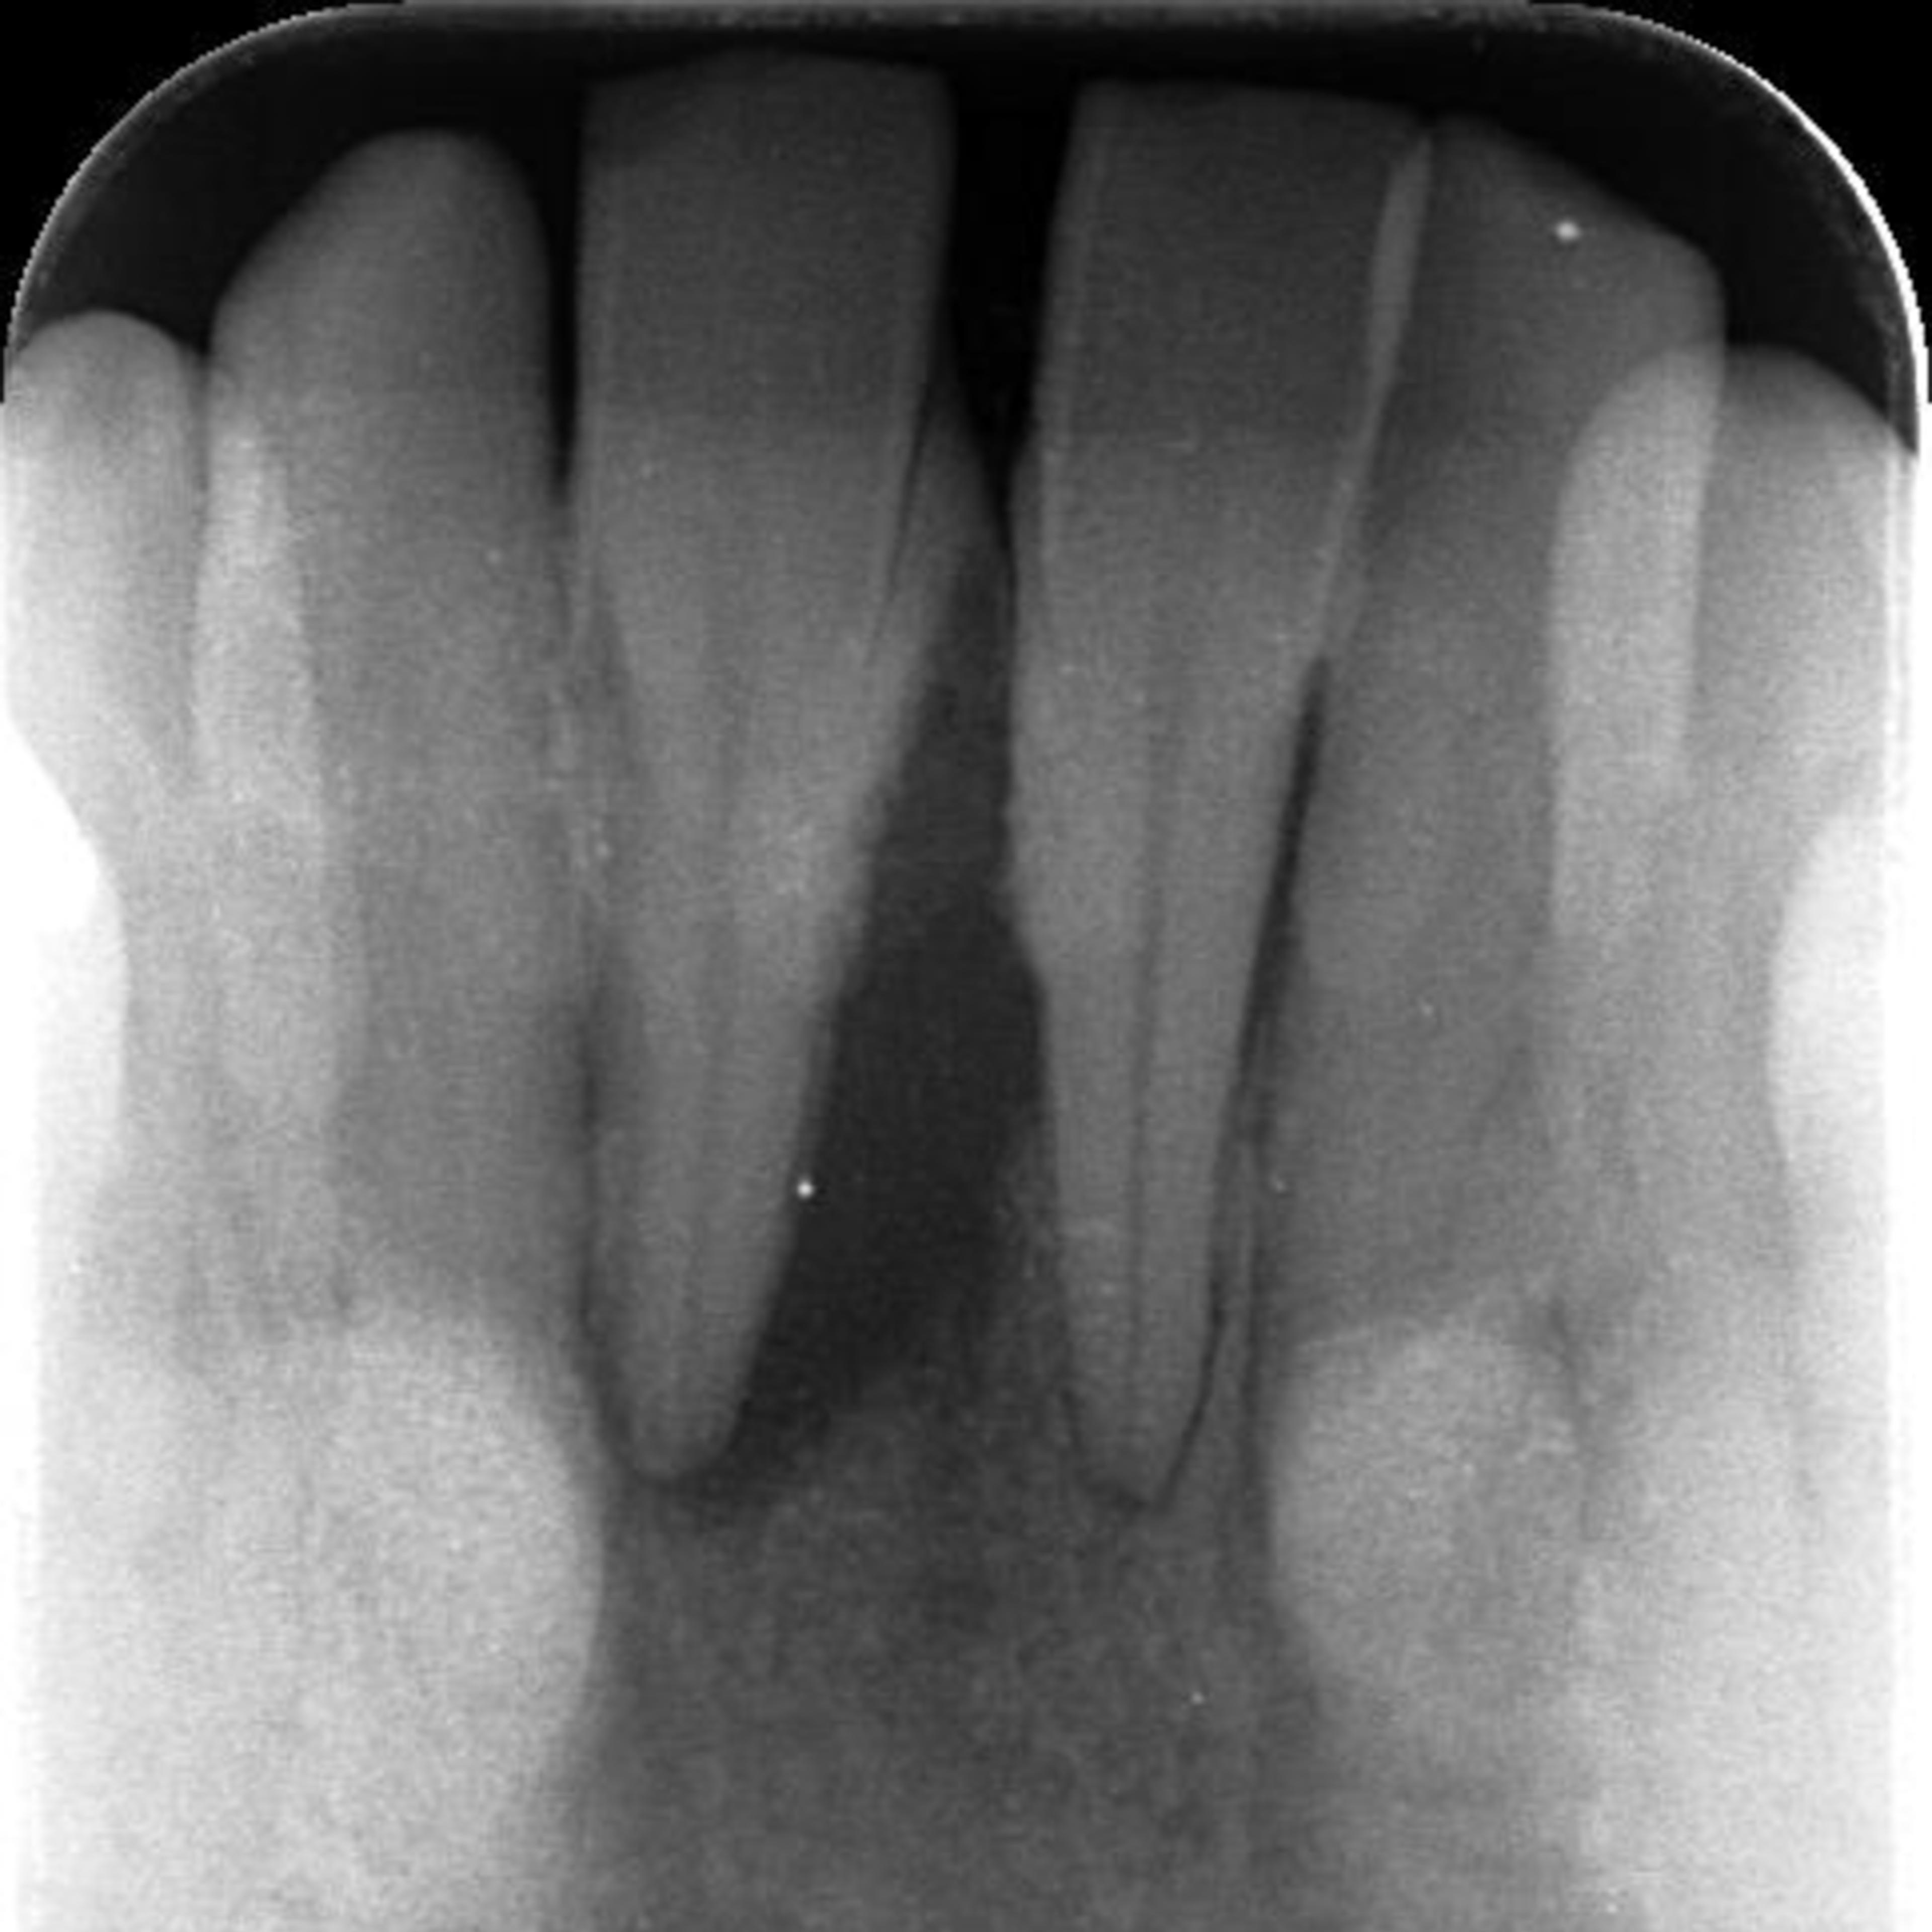

根尖に及ぶ透過像、黒い部分に骨はほとんどない。

根尖にまで及ぶ透過像

右下1をフォーカスしてみると、根尖に及ぶ透過像がみられます。画像の中央黒い部分になりますが、ここには歯を支える骨はありません。歯周ポケットの深さはもはや測定不可

教科書的には間違いなく抜歯となりますが、ここで諦めるのはまだ早く、回復出来る可能性もあります。原因除去療法により治療を進めることにいたしました。